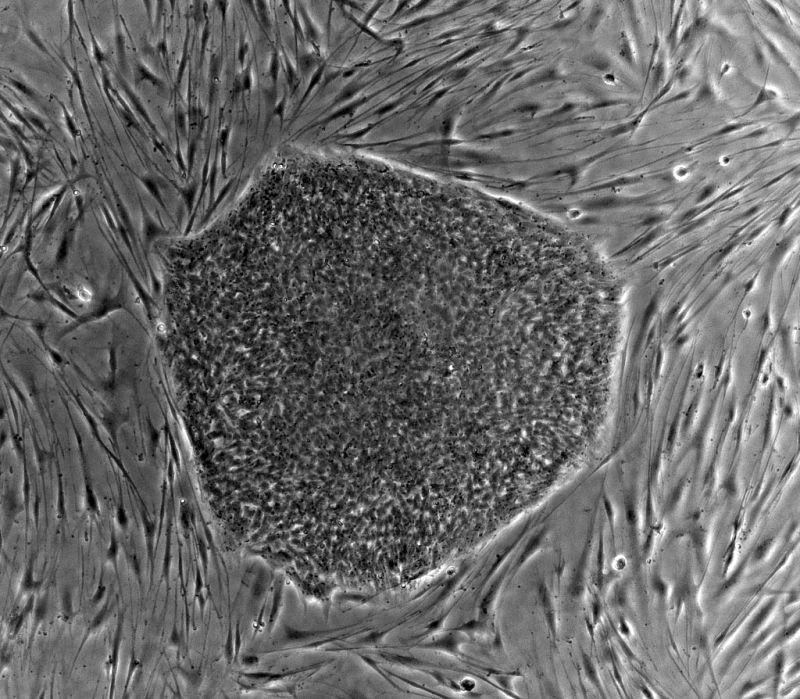

El prestigioso científico oncológico estadounidense Robert Weinberg,  Premio Príncipe de Asturias de Investigación en 2004, ha advertido de que aún faltan "muchos años" para conseguir una terapia efectiva contra la metástasis, responsable de nueve de cada diez muertes por cáncer.

El estadounidense ha explicado que la metástasis ha estado tradicionalmente envuelta en "misterio" al desconocerse cómo las células cancerígenas primarias llegaban a desarrollarse en otros lugares del cuerpo.

Sin embargo, el trabajo desarrollado la última década por la comunidad científica ha permitido "empezar a entender con gran precisión los procesos moleculares y los mecanismos bioquímicos que permiten a las células cancerígenas desplazarse y expandirse a sitios diferentes", vía metástasis.

Una de las líneas en las que se trabaja es descubrir qué tumores pueden extenderse por metástasis y cuáles no llegarán a ser agresivos.